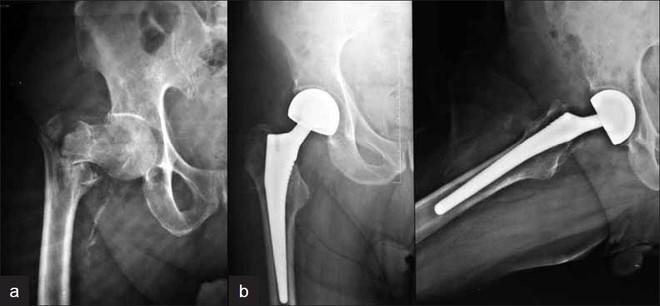

При неактивните или хронично болни пациенти, първично ендопротезиране трябва да се счита като основен метод на лечение за да се избегнат усложнения като разпад на остеосинтезата или остеонекроза.За ендопротезиране трябва да се мисли и при пациенти с артрит на тазобедрената става с фрактура.

Двуполюсно ендопротезиране.

Към него се пристъпва при силноразместени ,субкапитални фрактури и както и при съпътстващи заболявания като ревматоиден артрит и остеоартроза.Също така и при пациенти с паркинсон и други нервномускулни заболявания.Към двуполюсно ендопротезиране се пристъпва и при хора с онкологични заболявания.